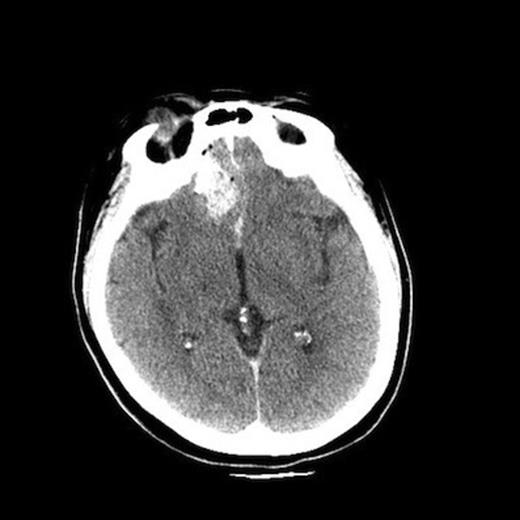

Upon removal of the hook, the patient was taken immediately to the CT scanner for a CT angiogram of the head. The CT scan demonstrated some leftward deviation of the anterior cerebral arteries, but there was no evidence of vascular injury or active hemorrhage. There was evident some recent parenchymal and subarachnoid hemorrhage with small subdural hygroma over the right frontal convexity. There was also hemorrhage and edema of the inferior orbit with displaced medial right orbital wall fracture. The globe was slightly dysmorphic, although the lens was intact, and there was no gross evidence of intraocular hemorrhage. The right orbit extruded such that 75% was beyond the orbital rim (Figure 4). A repeat CT scan was obtained two hours later which demonstrated no change and that the injury was stable.